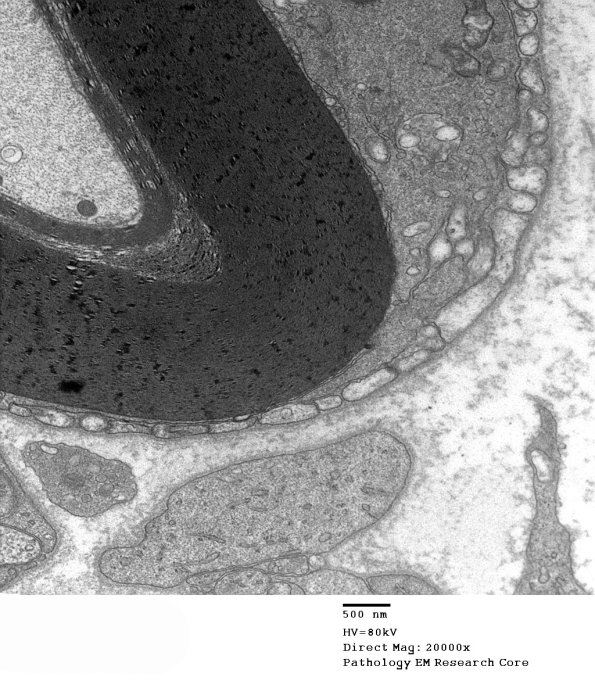

An early lesion where there is little myelin loss and only myelin debris in the macrophage. However, the tongues of macrophages are easy to recognize against the background of Schwann cell cytoplasm and small processes. (electron micrographs)